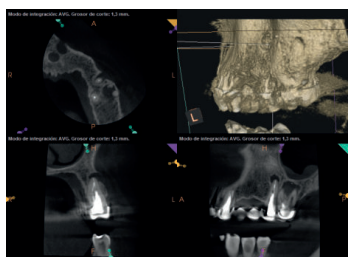

Para confirmar el origen endodóntico y el tamaño de las lesiones se realizaron exploraciones tomográficas con espesor de corte de 75 micras mediante CBCT CS8100 (Carestream Dental® ) en las que se evidenciaron lesiones periapicales radiolúcidas a nivel de 12, 11, 21 (con afectación bicortical), 25 y raíces vestibulares de 26 (Figuras 4 a 8).